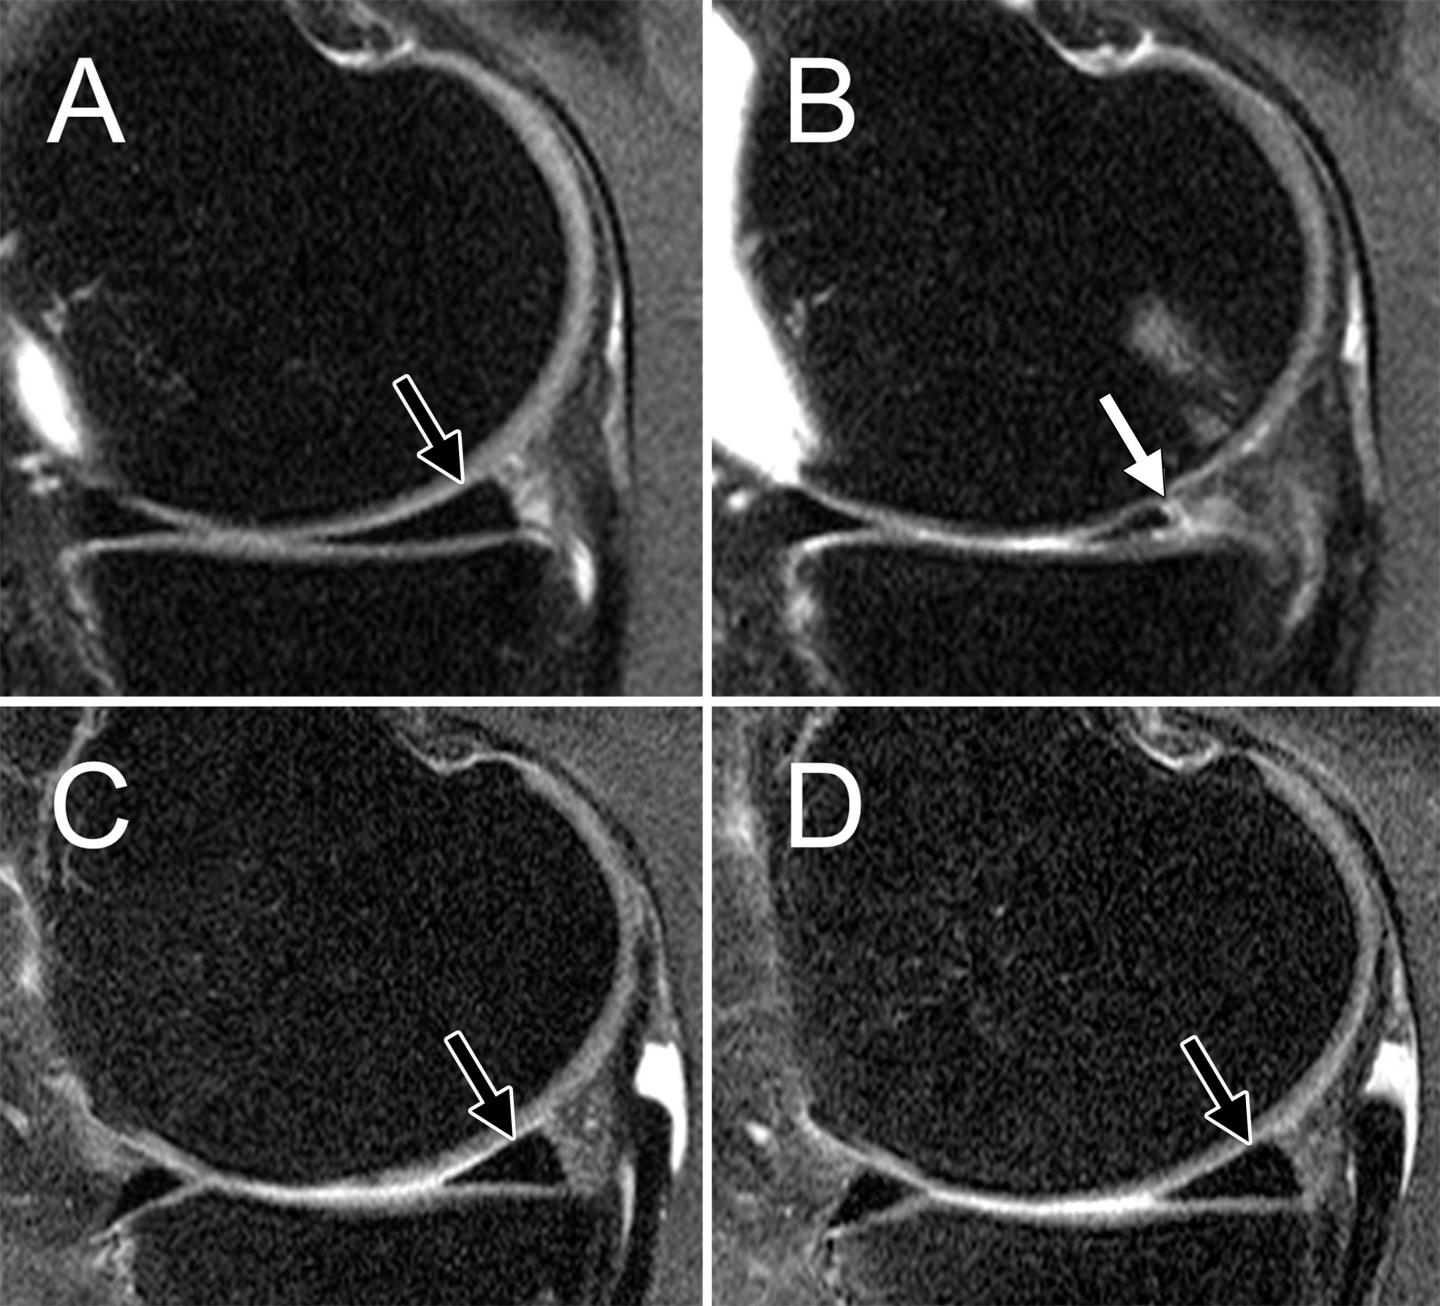

The research team investigated the association between weight loss and the progression of cartilage changes on MRI over a 48-month period in 640 overweight and obese patients (minimum body mass index [BMI] 25 kg/m2) who had risk factors for osteoarthritis or MRI evidence of mild to moderate osteoarthritis. Data was collected from the Osteoarthritis Initiative, a nationwide research study focused on the prevention and treatment of knee osteoarthritis. Patients were categorized into three groups: those who lost more than 10 percent of their body weight, those who lost five to 10 percent of their body weight, and a control group whose weight remained stable.

The results showed that patients with 5 percent weight loss had lower rates of cartilage degeneration when compared with stable weight participants. In those with 10 percent weight loss, cartilage degeneration slowed even more.

Not only did the researchers find that weight loss slowed articular cartilage degeneration, they also saw changes in the menisci. Menisci are crescent-shaped fibrocartilage pads that protect and cushion the joint.

"The most exciting finding of our research was that not only did we see slower degeneration in the articular cartilage, we saw that the menisci degenerated a lot slower in overweight and obese individuals who lost more than 5 percent of their body weight, and that the effects were strongest in overweight individuals and in individuals with substantial weight loss," Dr. Gersing said.